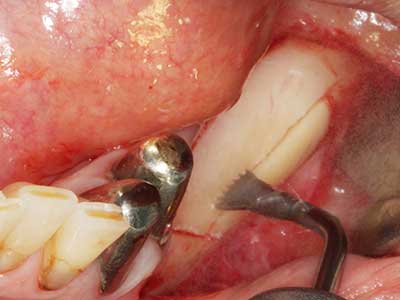

Пиезохирургията има допълнителни предимства при събиране на костни блокове. В допълнение към високата прецизност при остеотомията, описана по-горе, употребата на фините режещи накрайници значително намаляват загубата на материал. Голяма загуба на материал по време на събиране може да се очаква с дебелите накрайници, особено при употреба на борери Линдеман (Lakshmiganthan, Gokulanathan et al. 2012). Базалното разделяне, което е необходимо, особено за присадка на блок при ретромолар, е улеснено от специално създадени правоъгълни триони. В резултат на това, пиезохирургията е разглеждана като прецизна, улеснена и безопасна процедура за събиране на костни блокове в ретромоларното пространство (Happe 2007) (Фиг. 1-12).

Фиг. 1: Препарация на костно покритие с Piezomed (W&H Залцбург, Австрия).

Фиг. 3: Базалното разделяне на блока е по-лесно със специалните извити накрайници.